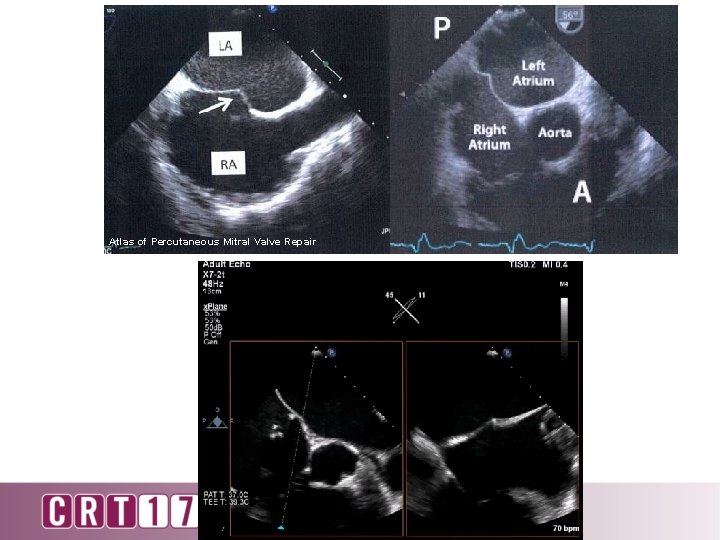

Atlas of Percutaneous Mitral Valve Repair

Puncture high and posterior Puncture low and posterior